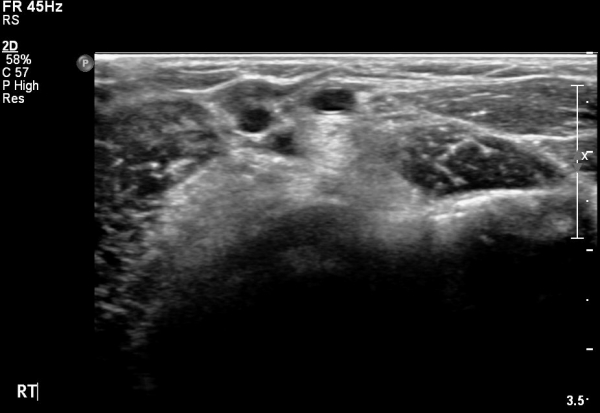

ÀÌµÎ¹Ú±Ù°Ç Á¾´Ü¸é°Ë»ç¿¡¼­ ¿ä°ñµ¹±âÀÇ µ¹Ãâ°ú °ñ±ØÀÌ °üÂûµÇ°í À̵θ·±Ù°ÇÀº Àú¿¡ÄÚ ºÎÁ¾°ú ¿¬°á ¼Ò½ÇÀÌ °üÂûµÊ(»çÁø 4, 5).